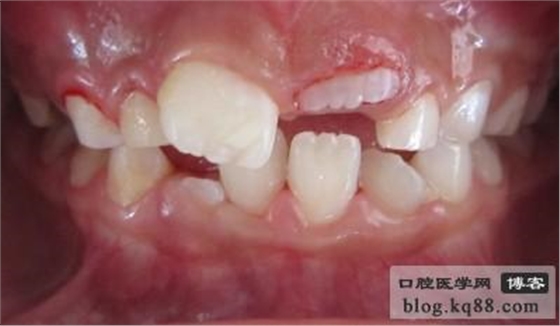

齦瓣切除助萌術(shù)后

3.沿遲萌牙的切端,由一側(cè)切角至另一側(cè)切角做唇腭側(cè)兩弧形切口,去除兩切口間的梭形齦瓣,露出牙的切端。

4.局部涂1%碘酊,紗布或棉球壓迫止血。